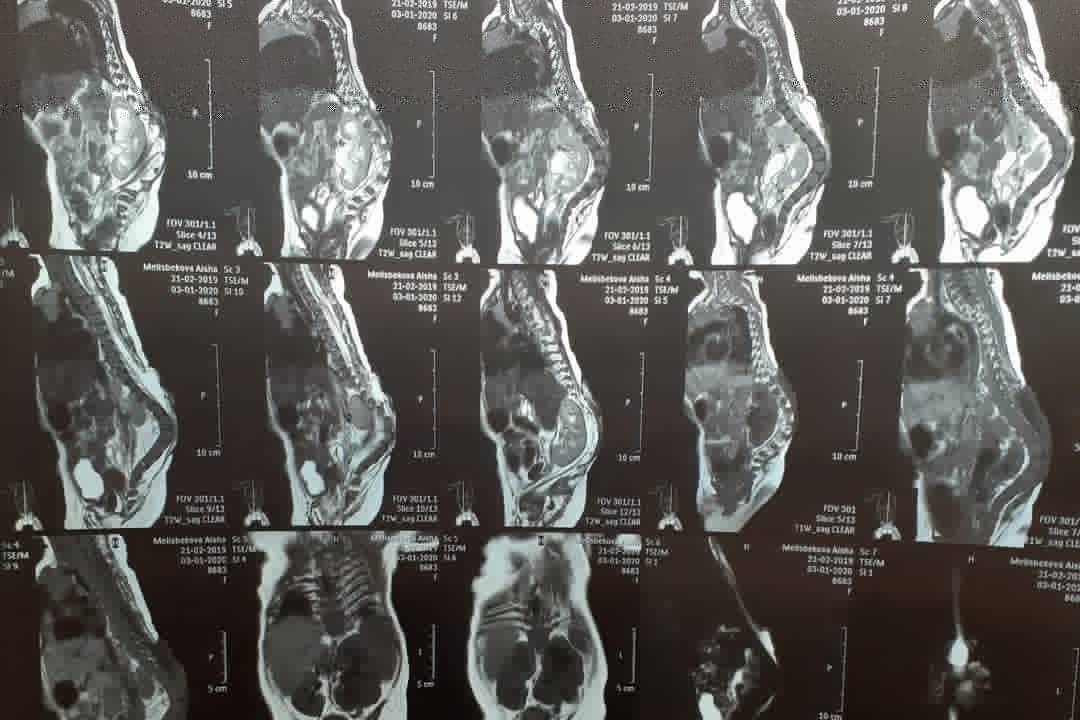

A️isha Melisbekoba was born with Spina Bifida myelomeningocele, syndrome of fixed spinal cord at 29 weeks. Doctors say that people born with this diagnosis will not live long. But with proper treatment on time she will survive. So far she had 2 operations on her spinal cord. Her spine is torn, spinal cord is protruding, and there is water in 1/3 of her head.

Diagnosis: CMD of the central nervous system Spina bifida myelomeningocele, fixed spinal cord syndrome. Kyphotic spinal deformity. Internal hydrocephalus, Arnold-Chiari type 2 anomaly. Peripheral paralysis of both legs. CHD, DMPP. CHF of the MPS hydronephrotic transformation of the left kidney, incomplete doubling of the left kidney. Urine and callus retention. Condition after: ventriculo-peritoneal shunting from 04/16/2019. And excision of the spinal hernia from 10/29/2019.

A️isha Melisbekoba was born with Spina Bifida myelomeningocele, syndrome of fixed spinal cord at 29 weeks. Doctors say that people born with this diagnosis will not live long. But with proper treatment on time she will survive. So far she had 2 operations on her spinal cord. Her spine is torn, spinal cord is protruding, and there is water in 1/3 of her head.

Diagnosis: CMD of the central nervous system Spina bifida myelomeningocele, fixed spinal cord syndrome. Kyphotic spinal deformity. Internal hydrocephalus, Arnold-Chiari type 2 anomaly. Peripheral paralysis of both legs. CHD, DMPP. CHF of the MPS hydronephrotic transformation of the left kidney, incomplete doubling of the left kidney. Urine and callus retention. Condition after: ventriculo-peritoneal shunting from 04/16/2019. And excision of the spinal hernia from 10/29/2019.